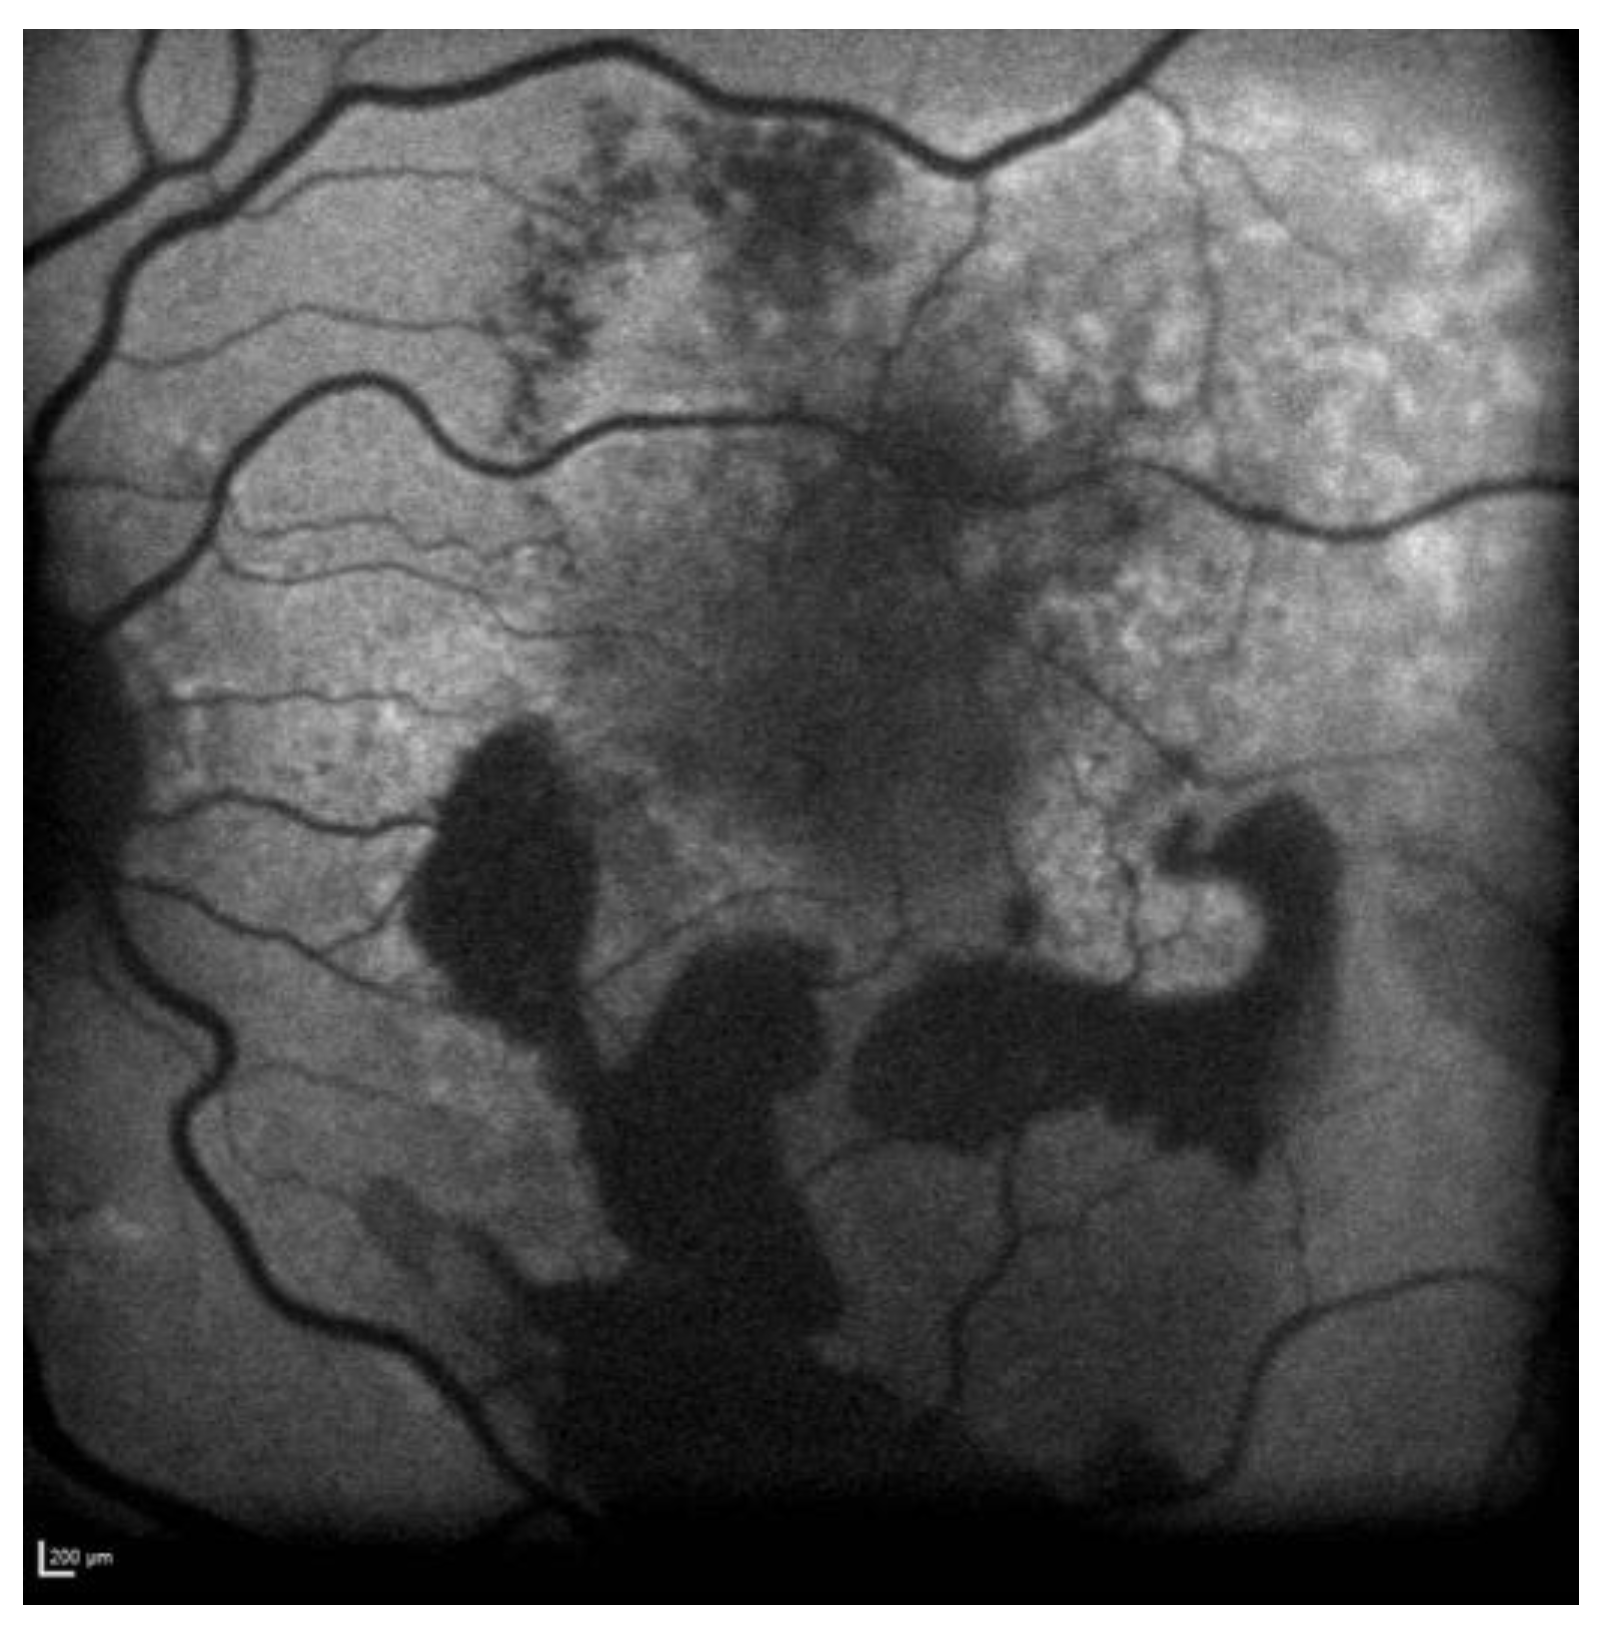

FAF revealed a hypoautofluorescent macular lesion in the left eye (Figure 8).

Figure 8.

Case 6. Heidelberg Spectralis blue autofluorescence shows a left eye macular hypoautofluorescent lesion.

The OCT scan showed a dry macula with drusen in the right eye and a type 1 MNV with PEDs, intraretinal and subretinal fluid, subretinal haemorrhage, and a haemorrhagic BALAD in the left eye (Figure 9A).

Figure 9.

Case 6. (A) Heidelberg Spectralis optical coherence tomography shows a type 1 MNV with fibrovascular pigment epithelial detachment, subretinal and intraretinal fluid, and haemorrhagic BALAD in the left eye. (B,C) Heidelberg Spectralis optical coherence tomography shows a good response after a year and two years of intravitreal anti-VEGF treatment, respectively.

The OCTA scan confirmed the presence of the left MNV.

A T&E regimen with anti-VEGF intravitreal injection therapy was commenced. The patient showed an initial good response to the treatment (Figure 9B). Unfortunately, over the following years, the worsening of the condition was observed despite treatment. Thus, the patient switched to a different anti-VEGF molecule.

To date, the patient is still on treatment. The left BCVA was 0.4 logMAR when last examined. The last OCT scan showed intraretinal fluid and an improved BALAD (Figure 9C).

Figure 10 shows Optos Ultra-widefield colour and autofluorescence imaging of the left eye macular lesion two years after the start of the treatment.

Figure 10.

Case 6. Optos Ultra-widefield colour and autofluorescence imaging of the left eye after two years of intravitreal anti-VEGF treatment, showing a yellowish (A) and hypofluorescent (B) macular lesion. The retinal haemorrhage was fully resolved (A,B).